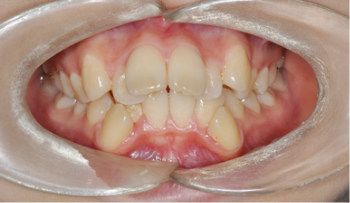

​​​​Case 05. 비수술 교정 치료

아래턱이 위턱보다 앞으로 나와 있으며, 치아도 반대로 교합되는 경우를 말합니다.

또한 발음이 부정확하고 저작(씹는 기능)장애가 있기도 합니다. 주걱턱은 얼굴 길이의 문제나 비대칭을 동반하는 경우가 많습니다. 부조화가 심한 경우, 악교정수술을 동반한 교정 치료를 통해서 치료할 수 있으며 습관이나 기능상에 의한 주걱턱은 교정 치료를 통해 해결할 수 있습니다.

교정 치료 Before & After

• 비수술 교정 치료 교정 치료 전

Before

• 비수술 교정 치료 교정 치료 후

After